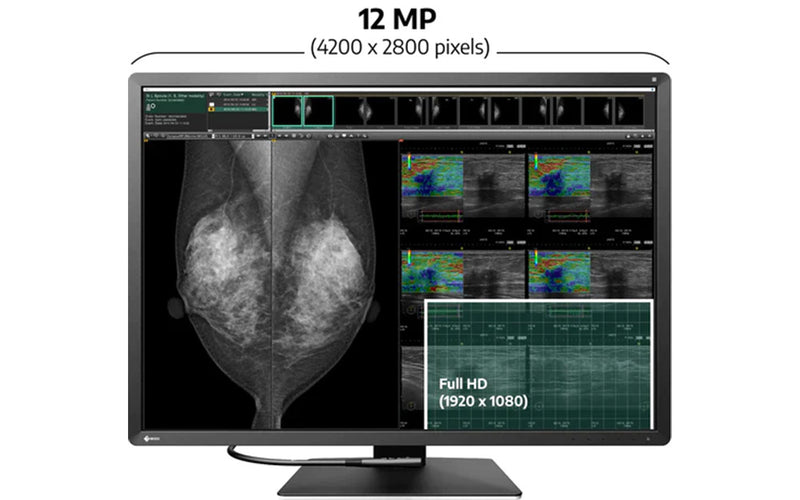

Εμφανίστε διάφορες εικόνες σε μια εξαιρετικά υψηλή ανάλυση 12 megapixel (4200 x 2800 εικονοστοιχεία) μεμονωμένη οθόνη με τη διάταξη της ελευθερίας της εικόνας. Παρέχει βελτιωμένη ορατότητα σε σύγκριση με περιβάλλοντα πολλαπλών οθονών, οδηγώντας σε μεγαλύτερη απόδοση.

Το Eizo Radiforce RX1270 συνειδητοποιεί την εξαιρετικά υψηλή ανάλυση των 12 megapixel σε οθόνη 30,9 ιντσών. Ο νέος σχεδιασμός είναι πιο συμπαγής σε σύγκριση με δύο συμβατικούς οθόνες 5 megapixel που χρησιμοποιούνται δίπλα-δίπλα. Όλα αυτά, ενώ περιλαμβάνουν ενσωματωμένο φως άνεσης και εσωτερική τροφοδοσία που δεν επιβάλλει στον χώρο εργασίας.

Το EIZO RADIFORCE RX1270 έχει λάβει την εκκαθάριση FDA 510 (k) από την αμερικανική Υπηρεσία Τροφίμων και Φαρμάκων για την τομοδυνθεσμό του μαστού και τη μαστογραφία. Αυτό εξασφαλίζει ότι το eizo radiforce rx1270 μπορεί να εμφανίσει λεπτομερείς εικόνες προβολής του μαστού όπου είναι απαραίτητη η υψηλή απόδοση.